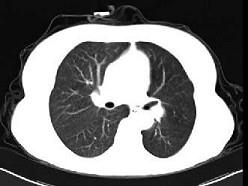

男,45岁,外伤后行CT检查如图,最可能的诊断为 ( )A、肺大疱B、支气管囊肿并感染C、左主支气管断裂D、畸胎瘤E、支气管肺炎

问题 男,45岁,外伤后行CT检查如图,最可能的诊断为 ( )

选项 A、肺大疱 B、支气管囊肿并感染 C、左主支气管断裂 D、畸胎瘤 E、支气管肺炎

答案 C